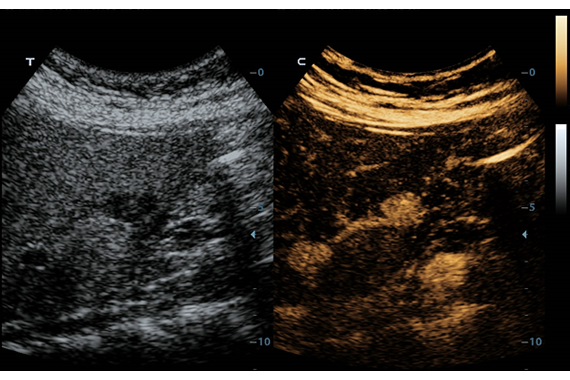

Система ультразвукового исследования Mindray DC-60 EXP X-INSIGHT является новейшей разработкой для проведения комплексных обследований на высшем уровне. Она обеспечивает решение самых сложных задач в таких областях, как кардиология, акушерство и гинекология, сосудистые заболевания, педиатрия и многие другие.

DC-60 EXP X-INSIGHT - это современный стационарный УЗИ-аппарат с функцией сенсорного управления и очищенной гармонической визуализацией, обеспечивающей лучшее контрастное разрешение и технологию 4D-визуализации. Он оснащен 21,5-дюймовым монитором, который может поворачиваться на 180 градусов, что удовлетворяет потребности врачей в качественной ультразвуковой диагностике.

• PSH™ - технология гармонической визуализации с фазовой инверсией.

• iBeam™ - режим многолучевого компаундинга.

• iClear™ - адаптивный режим шумоподавления.

• Echo Boost™ - режим улучшенной визуализации для кардиологии.

• HR Flow - режим отображения кровотока с высоким временным и пространственным разрешением для точной и однородной визуализации сосудов, в том числе самых мелких.